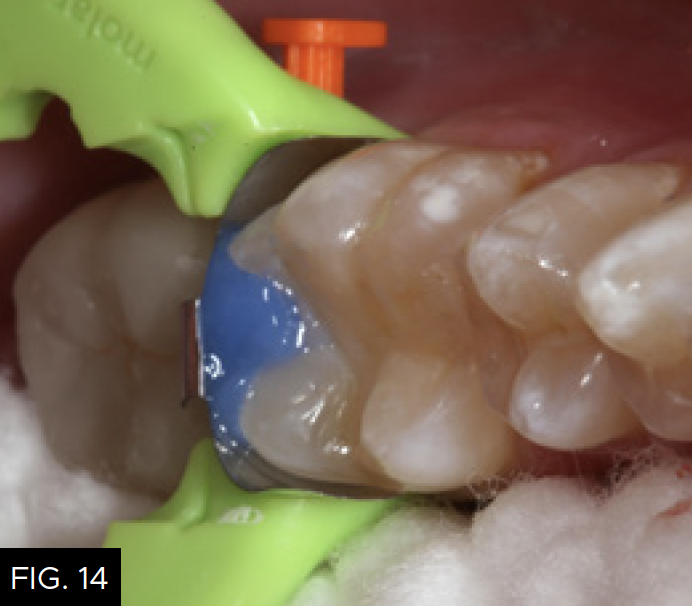

After a five-second etch of the restorative margins with 37% phosphoric acid, a surface sealant (Seal-N-Shine, Pulpdent) is placed with a microbrush, air thinned, and light-cured for 20 seconds. Surface sealants help to seal any microscopic marginal imperfections that may remain after the finishing and polishing process. The same restorative steps are performed for tooth number 19 (36). (FIG. 14 and 15)

A view down the central groove of tooth number 19 (36) is shown after placement of the composite material in the proximal box portion of the cavity preparation. Note that the marginal ridge has a definite facial and lingual component separated by a secondary groove that emanates from the distal pit of the tooth.